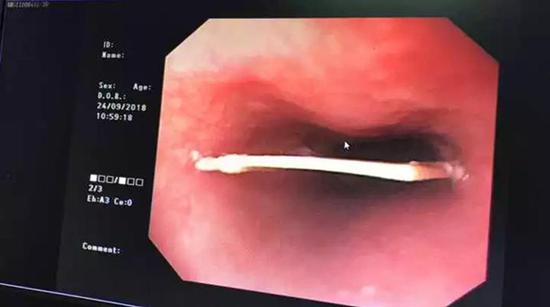

卡在食管的如刀一样的骨骼取异物欢迎转载我的文章,如果你想阅读更多